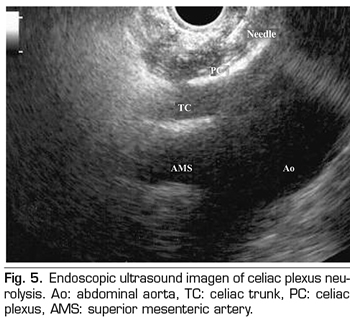

Percutaneous technique

The percutaneous technique is performed using a retrocrural posterior approach, usually guided by fluoroscopy (Figure 6). The lesions can be performed by conventional radiofrequency or using neurolytic agents as in the celiac plexus.

The splanchnic nerves are three nerves that are born from the thoracic sympathetic chain and are arranged laterally in the spine: 1) The greater splanchnic nerve is formed by the sympathetic preganglionic fibers from T5 to T9, 2) the minor splanchnic is formed by the fibers from T10 and T11, and 3) the inferior splanchnic, by the fibers coming from T11 and T12. All of them converge on the lateral face of the T11 and T12 vertebrae - ideal place for the performance of a neurolysis - and run parallel until they cross the diaphragm and join the celiac plexus.